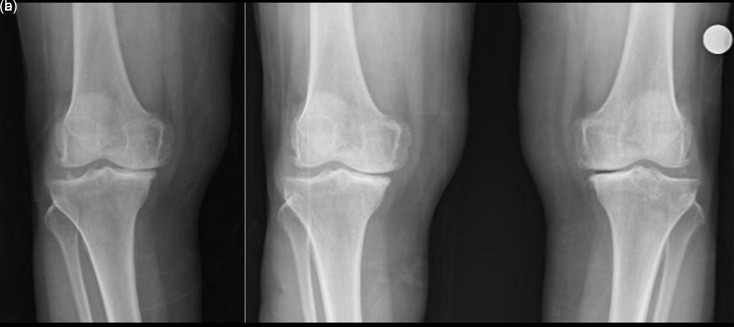

Objective: This study aimed to evaluate how single-leg weight-bearing and double-leg weight-bearing radiographs a!ect knee osteoarthritis assessment and treatment planning. Methods: Fifty orthopedic physicians were asked to assess the knee radiographs of 10 female patients (mean age: 68 ± 6.6 years) presenting with knee pain. The radiographs were obtained in both double-leg and single-leg weight-bearing positions. Physicians were asked to determine the appropriate treatment plan (conservative management, unicondylar knee replacement, or total knee replacement). If they opted for surgical intervention, they were further asked to specify which prosthetic material they required to be available during surgery (a unicondylar knee prosthesis, both unicondylar and total knee prostheses, a total knee prosthesis, both total and revision knee prostheses). Treatment plans based on double-leg and single-leg weight-bearing radiographs were compared. Results: Conservative management was more frequently selected based on double-leg weight-bearing radiographs (P < .001). In contrast, the requirement for additional surgical materials was significantly higher for single-leg weight-bearing radiographs (P < .001). Specifically, 53.6% of physicians preferred having both total and revision knee prostheses available based on double-leg weight-bearing images, compared to 64.2% for single-leg images. Moreover, 31.2% of physicians upstaged their treatment plans after reviewing single-leg radiographs. Additionally, 13% of physicians opted for a total knee prosthesis based on double-leg weight-bearing images, whereas this proportion increased to 29% with single-leg weight-bearing images. Conclusion: Single-leg weight-bearing radiographs prompted more invasive treatment decisions, highlighting their clinical utility in detecting pathology that may influence surgical planning. Level of Evidence: Level IV, Diagnostic Study.